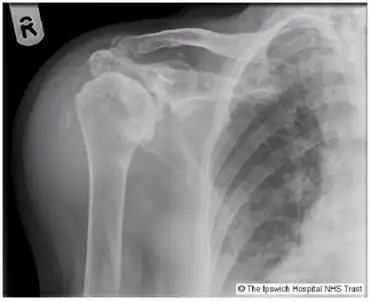

| Milwaukee shoulder syndrome X-ray. | |

Milwaukee shoulder syndrome (MSS) (apatite-associated destructive arthritis/Basic calcium phosphate (BCP) crystal arthritis/rapid destructive arthritis of the shoulder[1] is a rare[2] rheumatological condition similar to pseudogout, associated with periarticular or intra-articular deposition of hydroxyapatite or basic calcium phosphate (BCP) crystals. While primarily associated with the shoulder joint, it can affect any joint in the body below the head.[3] Along with symptomatology, the disease typically presents with positive radiologic findings, often showing marked erosion of the humeral head, cartilage, capsule, and bursae. Though rare, it is most often seen in females beginning in their 50s or 60s. Patients often have a history of joint trauma or overuse, calcium pyrophosphate dehydrate crystal deposition, neuroarthropathy, dialysis-related arthropathy or denervation.[2]